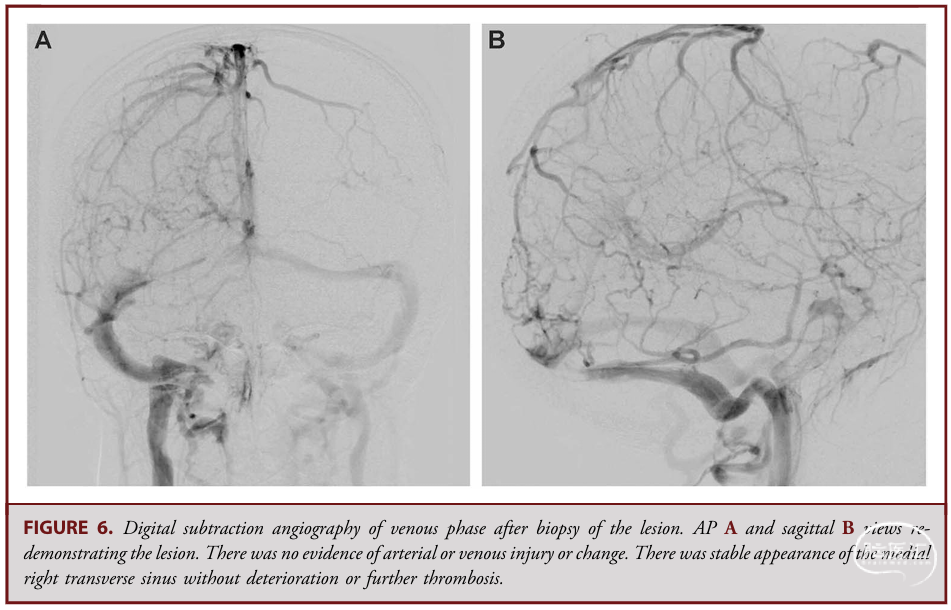

✔ 术后立即进行血管造影+锥形束CT,本例证实:无动静脉损伤、病变大小形态无改变。

✔ 上述细节很重要,说明操作未导致肿瘤碎裂脱落或静脉窦闭塞。